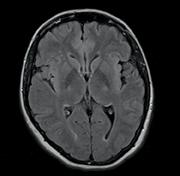

A magnetic resonance (MR) brain scan of a normal volunteer in one such study showed multiple microbleeds and white matter lesions.

“If this were a patient, I would say it was a stroke,” said Norbert Hosten, president of the German Radiological Society, speaking to journalists at a press conference at the European Congress of Radiology (ECR). But the volunteer showed no clinical signs of a stroke — or any other disease, said Hosten, who cited a multitude of potential gains that might come from population-based imaging.

But where do researchers draw the line? No action was taken, for example, in the patient who showed microbleeds and white matter lesions. What is so obvious that the radiologist has a duty to step in?